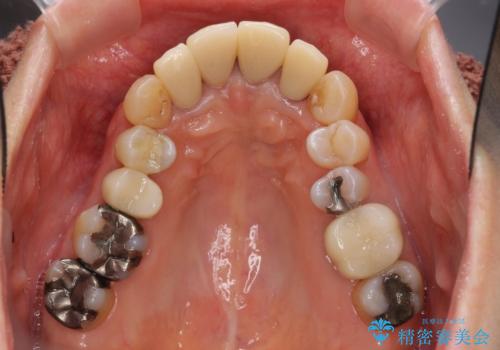

- 前歯の見た目・歯並び・銀歯の見た目の改善を求めて来院されました。

まずガタ付きの強い歯並びをマウスピース矯正インビザラインで整えたのち、セラミック治療による審美性の改善を計画します。